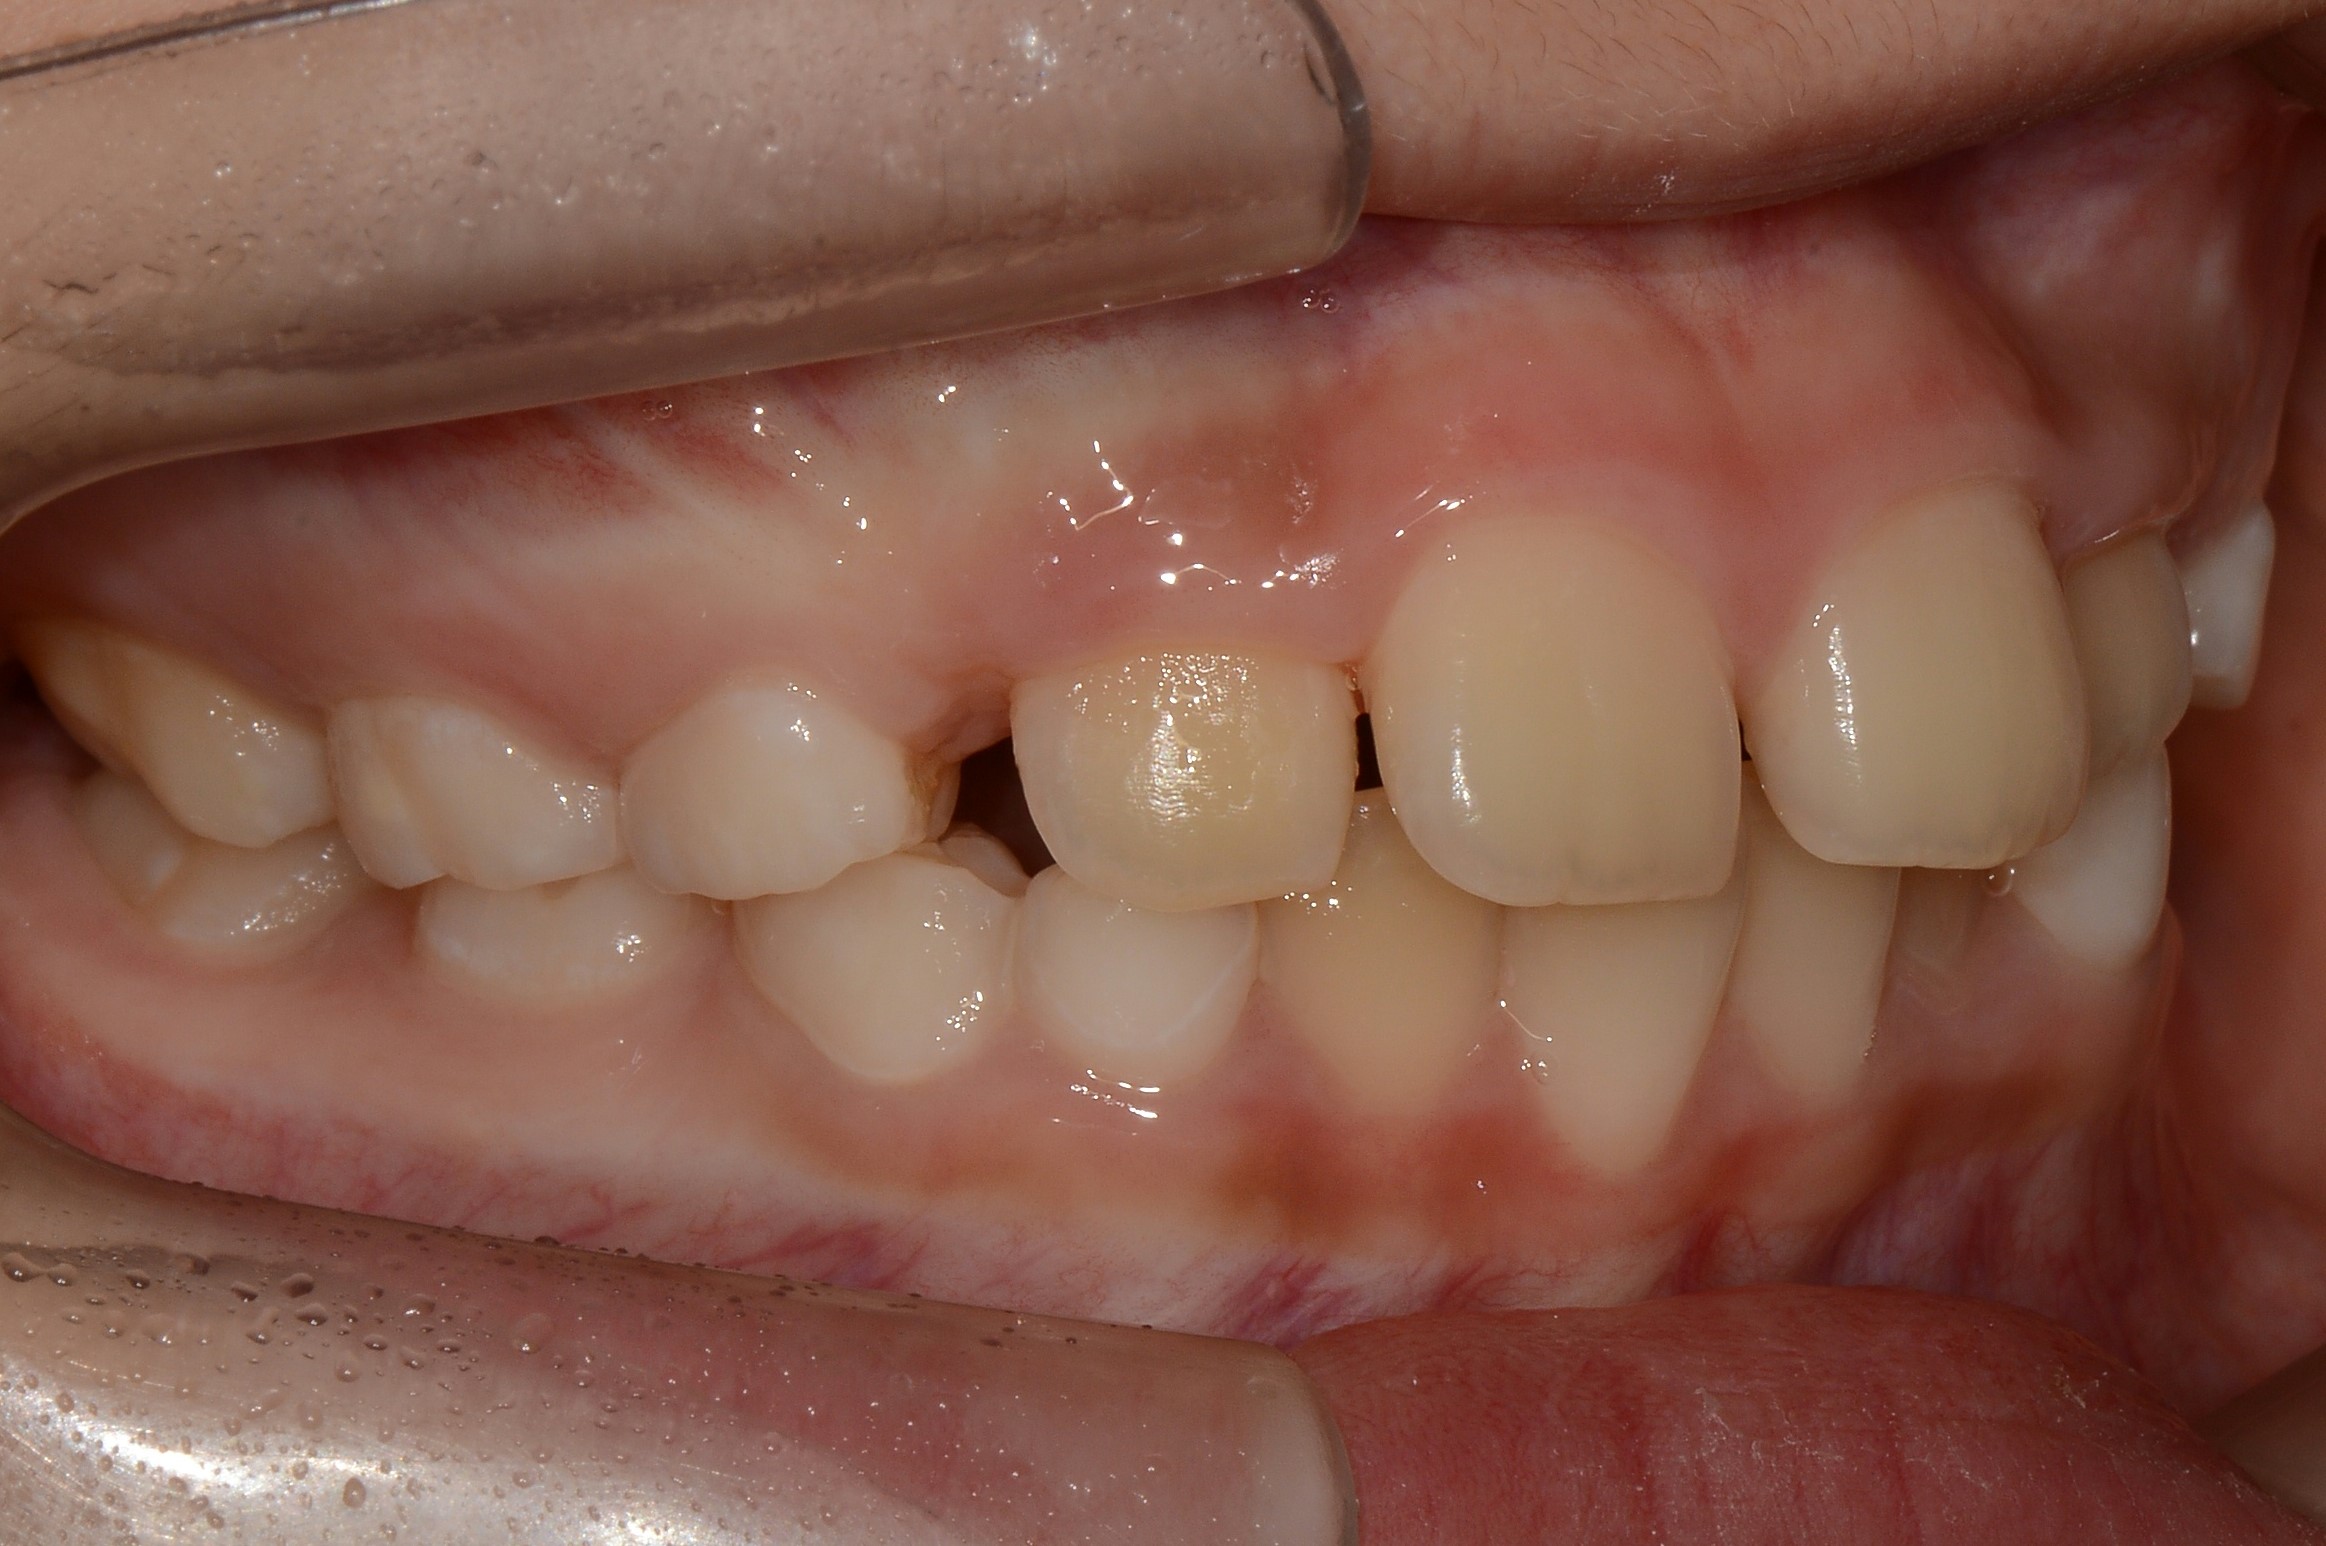

치료 전 사진입니다.